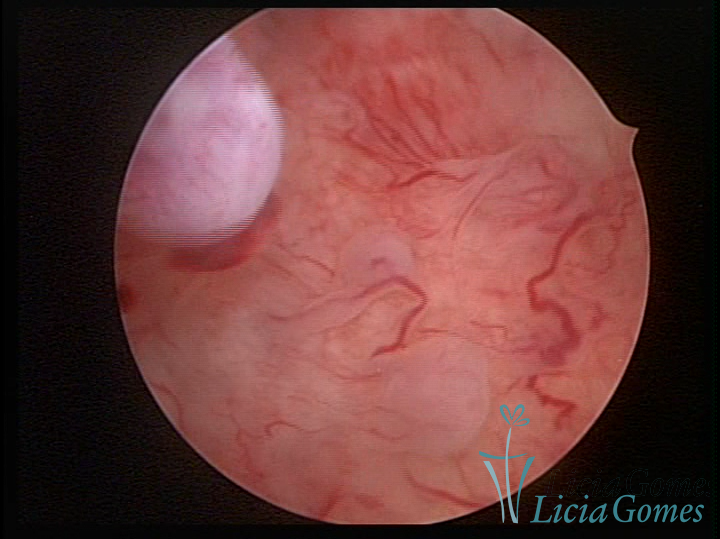

A histeroscopia permite analisar as características da superfície endometrial, não podendo avaliar a profundidade ou o grau de invasão miometrial.

Mas poderá verificar se as lesões são do tipo: focal; regional ou difusa

Este pode apresentar uma gama variável de aspectos macroscópicos, com aspecto pseudopolipoide; lembrando tecido cerebroide ou com reação deciduoide;a vascularização superficial é mais evidente e com vasos em formatos de saca-rolha ou espirais visualizando também a vascularização com atípias, com aumento do calibre dos vasos superficiais, pode ser encontrado também tecido em necrose, poderá haver um pequenos dendritos (papilomatoso).